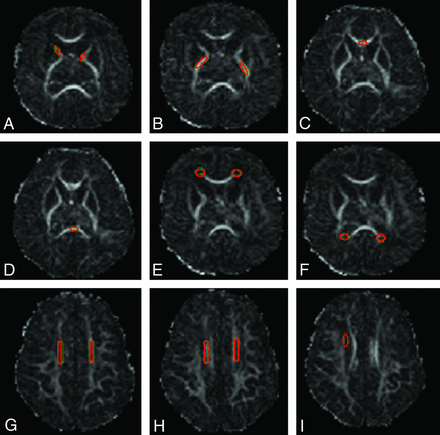

Image postprocessing and tensor calculations were performed by using MRIStudio software, Version 3.0.3 (Johns Hopkins University, Baltimore, Maryland; http://cmrm.med.jhmi.edu).17 Regions of interest were selected on the basis of prior published data.18,19 The following white matter ROIs were selected for further analysis: anterior and posterior limbs of the internal capsule, frontal and occipital periventricular zones, the centrum semiovale, the genu and splenium of the corpus callosum, and the subventricular zone. To minimize variability in region-of-interest placement, we used ImageJ, Version 1.44p (National Institutes of Health; http://imagej.nih.gov/ij) for development and placement of region-of-interest templates (1 for each region of interest) in the native space (Fig 1). All analyses were blinded to clinical variables and cranial sonography and anatomic MR imaging findings. Fractional anisotropy (FA) and mean diffusivity (MD) were measured for each region of interest.

Region-of-interest templates and placements shown on FA maps. A, Anterior limb of the internal capsule, B, Posterior limb of the internal capsule. C and D, Corpus callosum, genu and splenium. E, Frontal periventricular zone. F, Occipital periventricular zone. G and H, Centrum semiovale at 2 consecutive levels. I, Subventricular zone (right-sided). The same templates were used for all scans.